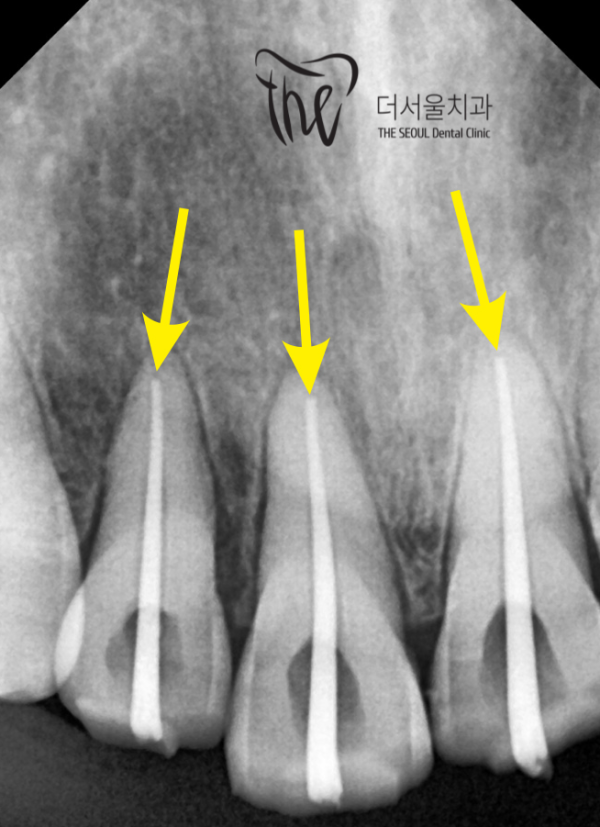

이 환자분은 '충치'가 없는 분이셨습니다.

하지만 앞니쪽에 충격이 있어 외상으로 인해 통증이 생기신 분인데요.

엑스레이를 보면, 치아 뿌리근처가 까만색으로 되어 있습니다.

바로 염증이 생긴 것 입니다.

This patient didn't have a cavity.

However, he has a shock on his front teeth and is in pain due to trauma.

If you look at the X-ray, the area near the tooth root is black.

It's an inflammation.